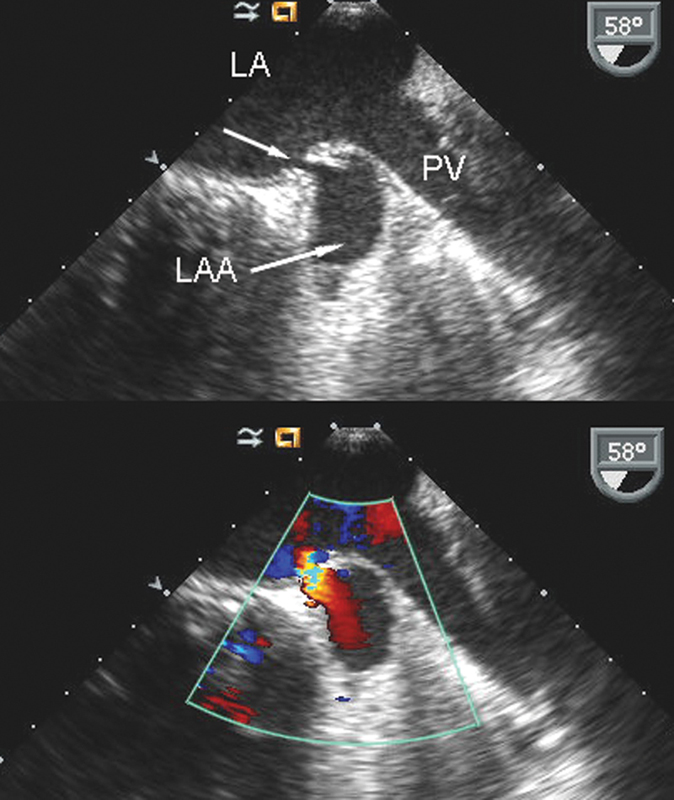

فحوصات تشخيصية لبعض امراض القلب والشرايين التاجية